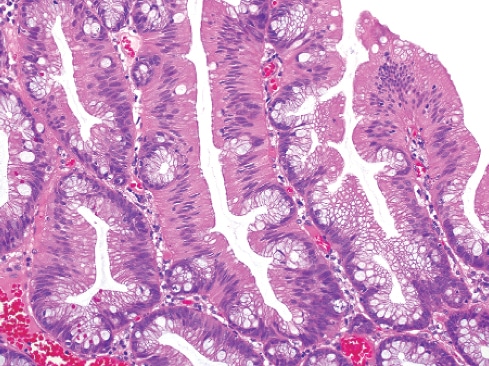

Featuring more than 1,000 high-resolution color graphics, Digestive System Tumours, the first volume of the fifth edition of the WHO series known as the Blue Books, brings a noticeable improvement in image quality and graphic design over the fourth edition, published in 2008. The book’s two-column layout, replacing the former three-column design, allows for enlarged images throughout. And this book is the first to be produced in both a print version and an online subscription version that includes whole-slide imaging.

The fourth edition of the WHO series set a whole new standard and raised the bar considerably from the third edition, Dr. Cree says. “And we are honestly trying to do the same with the fifth edition.” The new online subscription feature, for example, is intended not only to make user access easier but also to show significantly more content. “We have a whole-slide image for each diagnosis in the book. Whole-slide images allow us to get an overview of the entire section of the slide right down to the individual cells and see what is going on.” In addition, each paper in the book has a direct online link to the evidence that underpins the paper, he notes.

From the chapter “Genetic tumour syndromes of the digestive system,” juvenile polyposis syndrome.

Pathologists learn so much from their exposure to illustrations, he says, and high-quality graphics have always been a feature of the WHO Blue Books. “When you collect world experts together and they all have their archives of gross photographs and microscopic slides, you can produce the best examples and most classic illustrations of the features.”

Now, the incorporation of digital slides will allow an interactive experience for the reader, who will be able to look at not just a single snapshot, such as would appear in a book, but also different magnifications that can be examined more comprehensively. This capability has become practical only in the past few years, Dr. Klimstra says. The WHO has learned from the experience of PathPresenter, which has created an educational portal for digital slides that is now an entirely new feature of the WHO series.